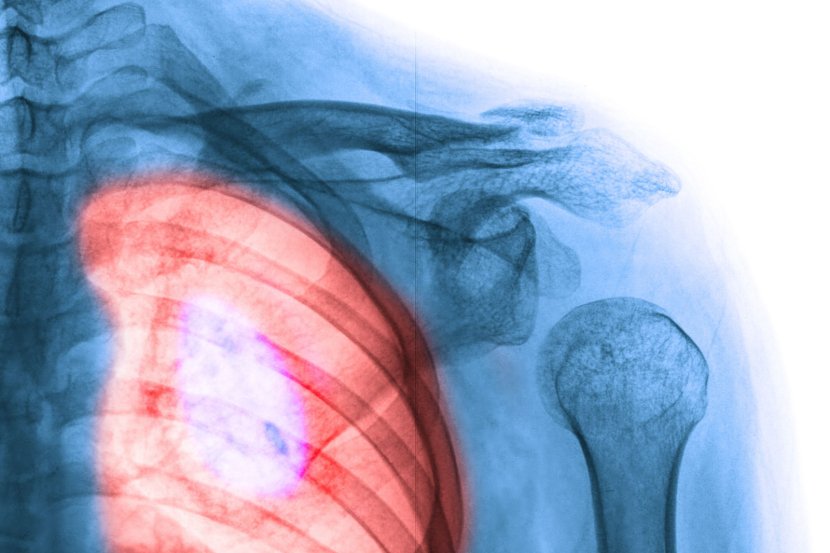

Jedna vrsta raka pluća ili adenokarcinomi ponekad reaguju na inicijalno efikasne tretmane tako što se transformišu u mnogo agresivniji sitnoćelijski karcinom pluća koji se brzo širi i ima nekoliko opcija za lečenje. Istraživači u Weill Cornell Medicine u laboratorijskim uslovima rasvetlili su ovaj problematičan proces, poznat kao histološka transformacija. Nalazi studije unapređuju saznanja kako mutirani geni mogu da pokrenu evoluciju raka i predlažu ciljeve za efikasnije tretmane.

Adenokarcinom je vrsta raka pluća koji može da se pretvori u sitnoćelijski karcinom

Sitnoćelijski ili mikrocelularni karcinom pluća je vrasta raka pluća najčešća kod pušača

Sitnoćelijski ili mikrocelularni karcinom pluća najčešće javlja kod teških pušača, ali se ovaj tip tumora razvija i kod značajnog broja pacijenata sa adenokarcinomom pluća, posebno nakon tretmana terapijama koje ciljaju na protein koji se zove receptor epidermalnog faktora rasta (EGFR), koji podstiče rast tumora. Novi tumori tipa sitnoćelijski ili mikrocelularni karcinom pluća  otporni su na anti-EGFR terapiju jer njihov rast podstiče novi pokretač karcinoma - visoki nivoi Myc proteina.